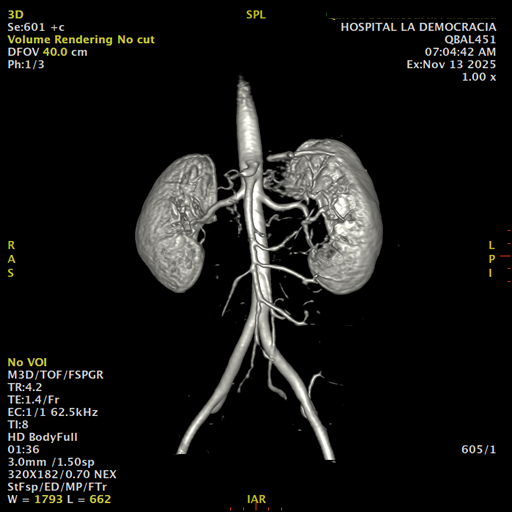

Paciente de sexo femenino, de 45 años de edad, refiere infecciones urinarias a repetición, no hay dolor, no refiere trauma, consulta por ardor al orinar, medico tratante le solicita resonancia abdominal, con énfasis en riñones, además un estudio de angiorenal.

Se prepara a paciente para ingreso a zona 4 del área de resonancia. Se coloca a paciente en decúbito supino, se canaliza en vena antecubital, se utiliza bobina de abdomen de 16 canales, se adquieren localizadores en tres planos, luego se procede a adquirir imágenes en diferentes planos, con secuencias echo spin y eco de gradiente, potenciadas a T1 y a T2.

Los sistemas colectores del riñón derecho y del riñón izquierdo, muestran alteración de sus calices primarios y secundarios, mostrando dilatación, la pelvis renal y el uréter se observan de características normales lo que indica que no hay proceso obstructivo.

Se observa dilatación del sistema calicial sin proceso obstructivo compatible con una anormalidad del desarrollo de los sistemas colectores de ambos riñones, definiéndose como una “megacaliosis”